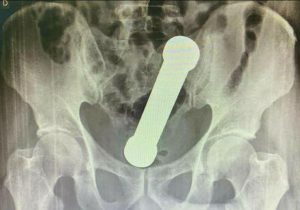

“An eight-inch dumbbell, weighing 2kg, has been removed from the rectum of a 54-year-old man after he arrived at A&E complaining of cramps and severe constipation.

Medics said the patient was “uncooperative” while he was being examined, so they decided to X-ray his abdomen.

They then found an object, that was later revealed to be a 2kg dumbbell, lodged firmly in the 54-year-old man’s rectum.